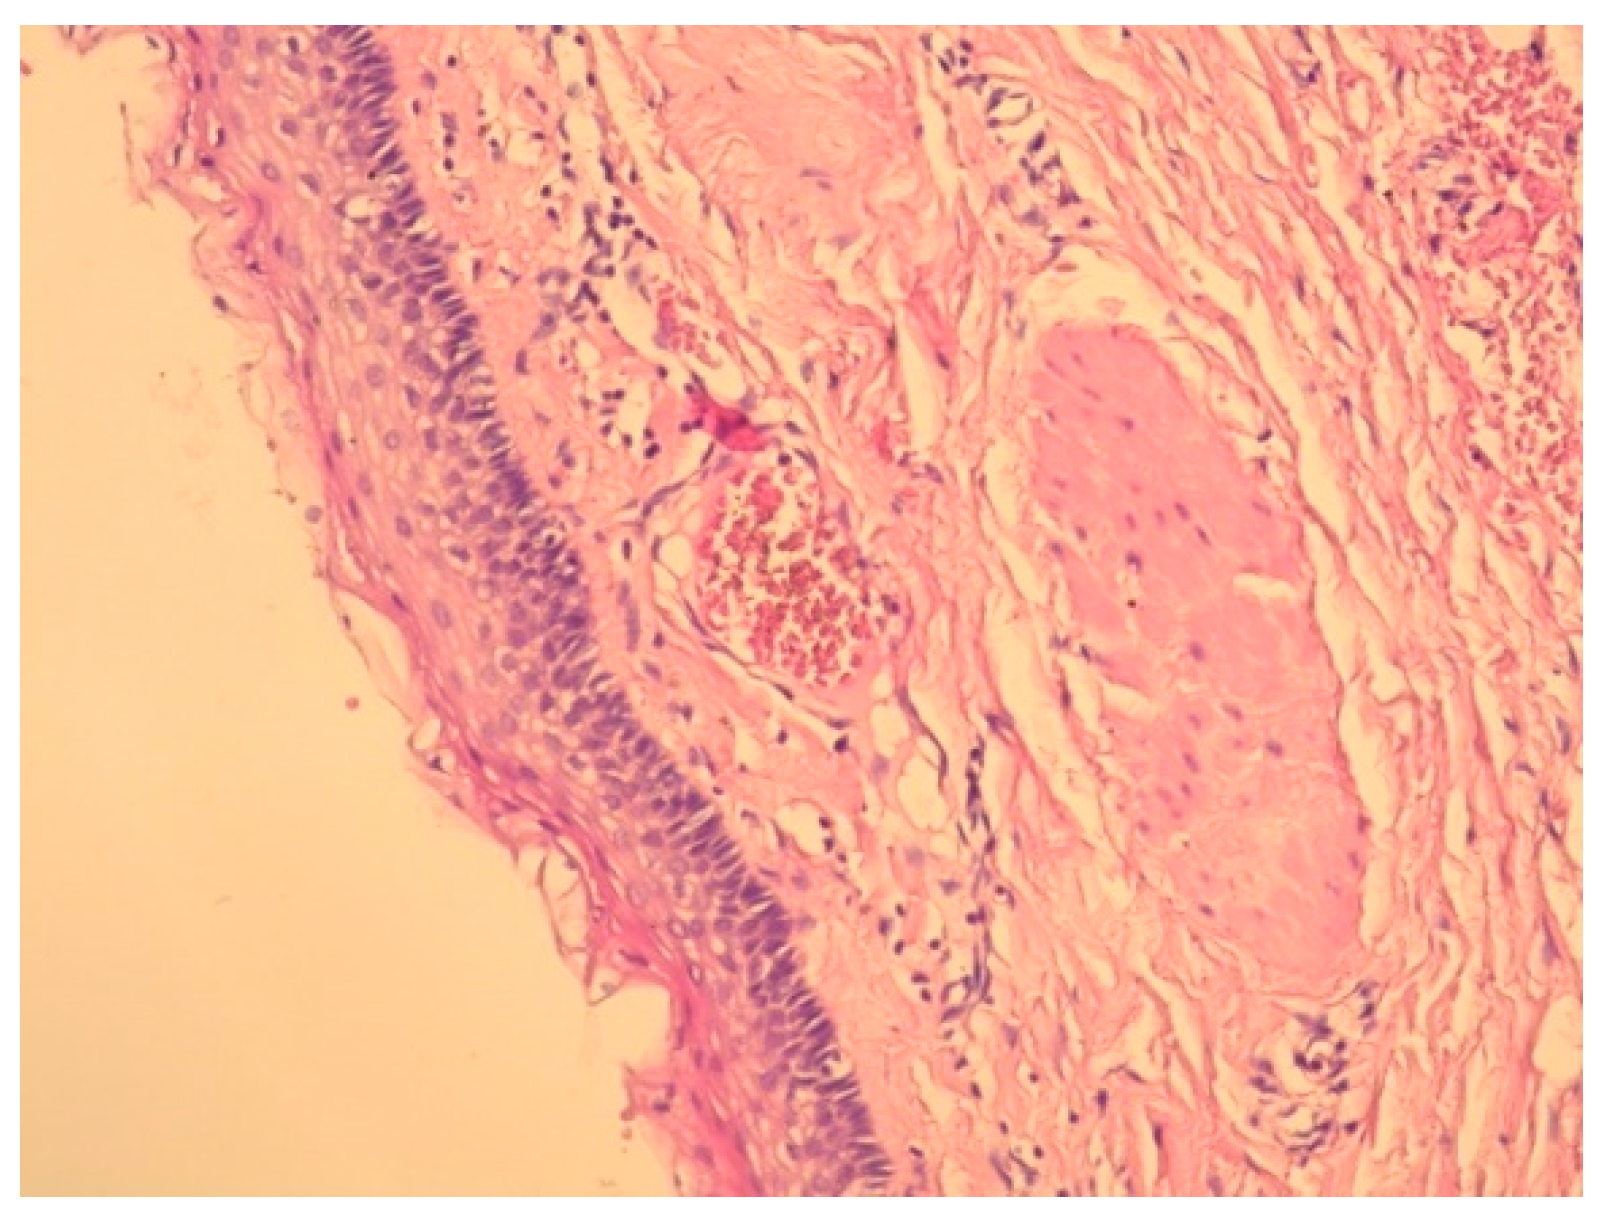

2. Case Presentation